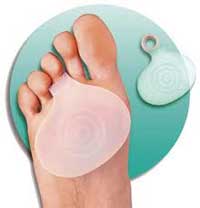

برداشتن فشار از سر استخوانهای کف پایی به وسیله پَدِمتاتارس، استراحت و استفاده از کمپرس یخ میتواند باعث بهبودی و درمان بیماری شود.

پد متاتارسال با پشتیبانی از قوس عرضی کف پا موجب برداشته شدن فشار از روی سر استخوانهای متاتارس(استخوانهای جلوی قوس عرضی پا) گردیده و فشارهای وارده به موضع را تقسیم و تعدیل می نماید. پد متاتارسال در بیماریهایی از قبیل متاتارسالژیا(التهاب سر استخوانهای متاتارس)، میخچه های سر متاتارسها، آرتریت روماتوئید و دفورمیتی هالوکس والگوس(انحراف شست پا به داخل) تجویز می گردد.

در هنگام استفاده از پد متاتارس،آنرا رابه گونه ای درکف پا جاسازی کنید که قسمت نیم دایره پد به طرف جلو بوده و قسمت برجسته آن کاملا عقب تر از سینه پا قرار گرفته و هیچ تماسی با نقاط حساس و دردناک سینه پا نداشته باشد.

باپوشیدن جوراب روی پد متاتارس ازجابجای آن جلوگیری نمایید. این پد در شرکت تولید تجهیزات ارتوپدی فنی R&R تولید و عرضه می شود.